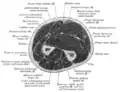

Cross-section through the middle of upper arm.

Cross-section through the middle of the forearm.